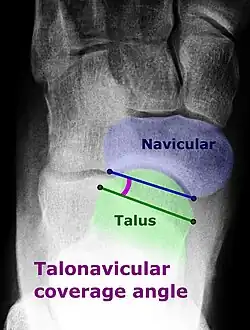

On weightbearing projectional radiography, pes cavus can be diagnosed and graded by several features, the most important being medial peritalar subluxation, increased calcaneal pitch (variable) and abnormal talar-1st metatarsal angle (Meary's angle).[17] Medial peritalar subluxation can be demonstrated by a medially rotated talonavicular coverage angle.[17]

Dorsoplantar projectional radiograph of the foot showing the measurement of the talonavicular coverage angle.

Dorsoplantar projectional radiograph of the foot showing the measurement of the talonavicular coverage angle. -